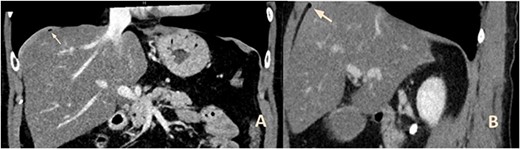

A 55-year-old male was hospitalized by the Department of Gastroenterology with nausea and vomiting over the past 2 weeks. He also mentioned diarrhea starting 2 days before admission. Further medical history revealed alcoholism. On clinical examination, he showed moderate abdominal distention and normal bowel sounds. There was no sign of peritonitis. His body temperature was within normal range. Laboratory findings showed elevated levels of transaminases, alkaline phosphatase and bilirubin. White cell counts and C-reactive protein were within normal range. A computed tomography (CT) scan of the abdomen showed free air distributed along the ascending colon and above the liver with punctum maximum in the right upper quadrant (Fig. 1). The patient underwent an emergency laparoscopy, which revealed no sign of perforation or bowl ischemia but showed air embedment in the mesenterium along the ascending colon (Fig. 2). Subsequent coloscopy revealed an unclassified inflammatory bowel disease manifesting in the rectum. Gastroscopy showed erythematous mucosa and epithelialized erosions. Endosonography showed mild chronic pancreatitis without duct obstructions or pseudocysts. Sonography and endosonography of the liver and bile ducts showed signs of alcoholic steatohepatitis, confirmed by liver biopsy. The patient discharged himself on Day 8 after the surgery.

CT of the upper abdomen with frontal (a) and sagittal (b) reconstructions showing the air bubbles above the liver (arrows).